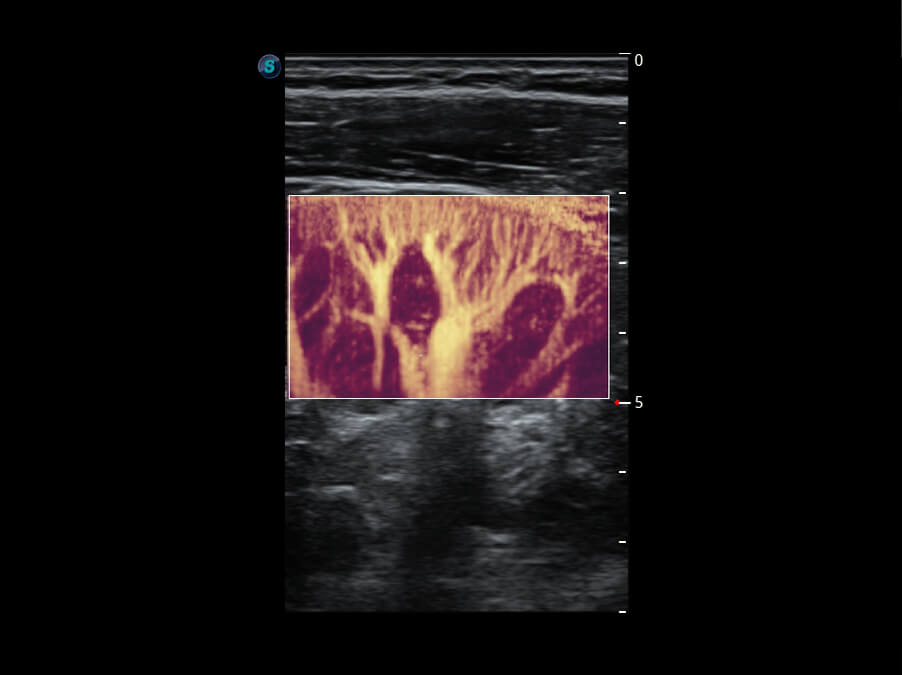

高分辨率容积成像 栩栩如生

超宽频带技术,为容积成像带来优质的二维图像基础,为您呈现丰富的结构细节,栩栩如生地展示宝宝的宫内形态以及各种组织的立体结构。